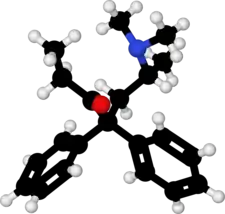

| Formula | C21H27NO |

| Molar mass | 309.453 g·mol−1 |

| 3D model (JSmol) | |